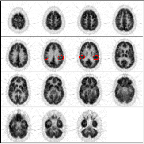

The first step in analyzing image quality is to look for artifacts. For example, this scan is too noisy.

This scan is too smooth.

This scan is just right! (with apologies to the author of "Goldilocks and The Three Bears")